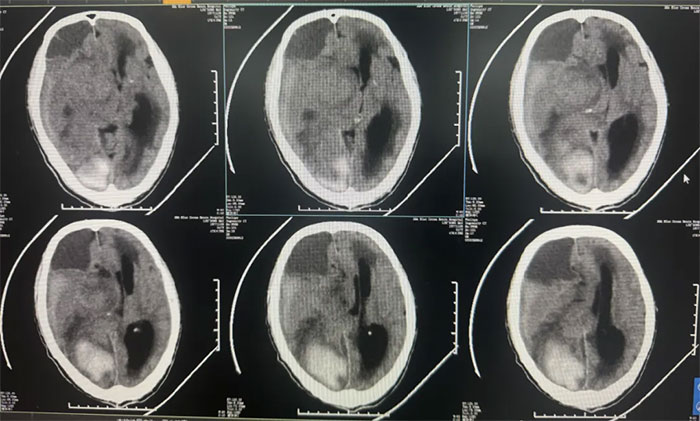

優(yōu)質(zhì)服務(wù) ︱ 抓住腦出血后“黃金康復(fù)期” 精心救治助患者恢復(fù)行走能力

腦出血往往起病突然、急性發(fā)作,即使在全力搶救后仍有較高的致殘、致死率,嚴(yán)重威脅著患者生命健康。規(guī)范的早期康復(fù)治療,則是提高患者生活質(zhì)量、防止疾病復(fù)發(fā)的重要手段,越早介入,獲益越大。...【詳細(xì)】